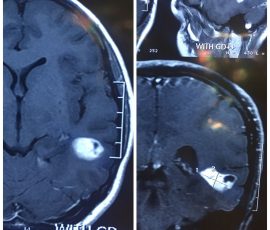

تشخیص تومور مغزی

- تصویربرداری با MRI برای مشاهده دقیق محل و اندازه تومور

| MRI مغز | نمایش دقیق محل، اندازه و شکل تومور |